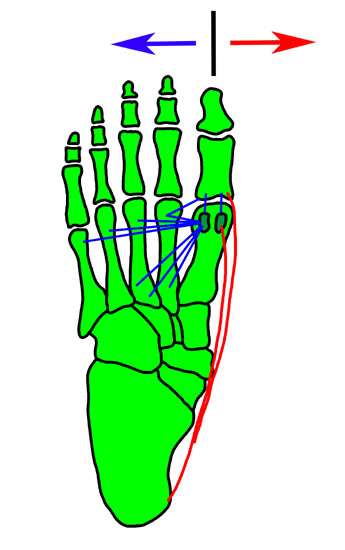

Zusammenhänge der adduzierenden und abduzierenden Muskelkräfte <a class=15, (Janis 1975)" title="Zusammenhänge der adduzierenden und abduzierenden Muskelkräfte 15, (Janis 1975)" width="345" height="550">

Abbildung 6: Zusammenhänge der adduzierenden und abduzierenden Muskelkräfte 15, (Janis 1975)

Veränderung der Sehnenvektoren bei Vorliegen eines Hallux varus<br><br>

Abkürzungen:<br>

EBH   M. extensor hallucis brevis<br>

EHL   M. extensor hallucis longus<br>

AdH  M. adductor hallucis<br>

AbH  M. abductor hallucis<br>

FHB-L    lateral

Abbildung 7